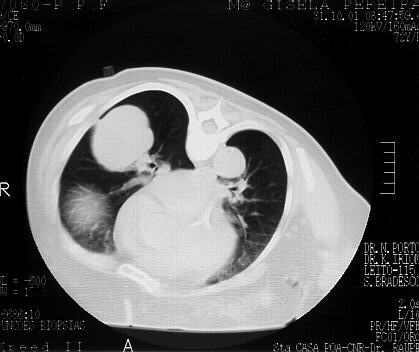

Chest CT demonstrating in the right lower lobe, a large mass with smooth contour and a fibrous conection with the pleura. Patient in position for the FNA procedure.